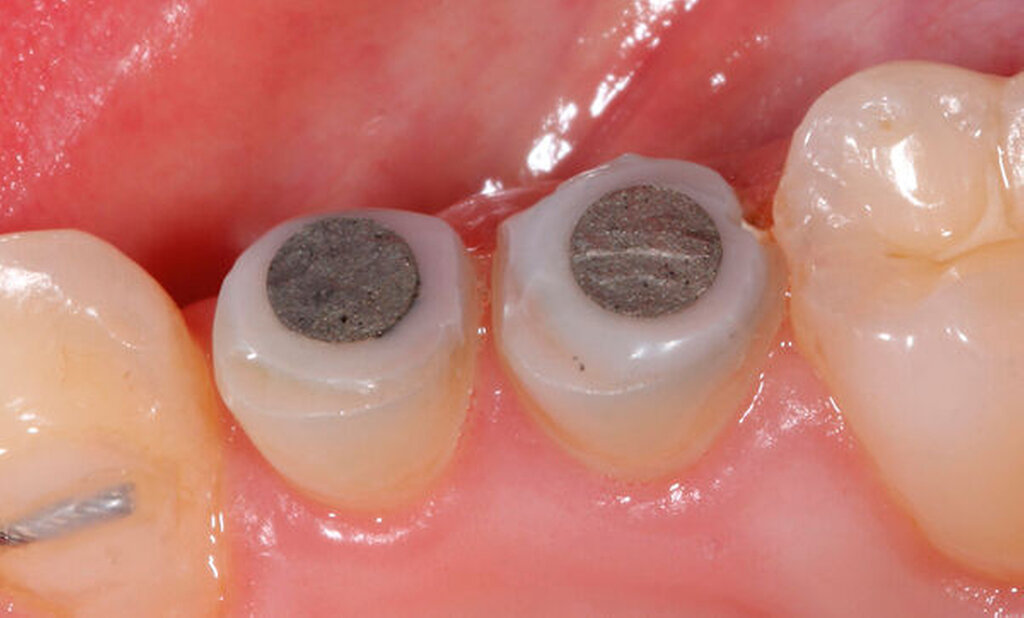

Als Hilfsmittel, die die Zugkräfte auf die betroffenen tief zerstörten Zähne übertragen können, eignen sich spezielle Magnet- oder Gummizug-Systeme (zum Beispiel Neodym-Scheibenmagnete; TMC Extrusion, Komet GmbH) (Abbildungen 12 und 13). Bei den Magnetsystemen ist in der Regel ein Abstand von 0,5 bis 2 mm zum Kontermagneten über einen Abstandshalter nötig. Der Kontermagnet wird in einer Tiefziehschiene oder in ein entsprechendes Methacrylatprovisorium mit Abstützung an den Nachbarzähnen einpolymerisiert. Die Zugkraft beeinflusst die Art der Extrusion. Kräfte mit circa 0,3 N verursachen eine verzögerte Extrusion um etwa 1 mm pro Woche. Die forcierte Extrusion erfordert mindestens 0,5 N, um eine Extrusion von mehr als 1 mm pro Woche zu bewirken [Krastl, 2004].

Die Extrusionzeit beträgt zumeist vier bis acht Wochen, wobei eine initiale, meist länger dauernde Phase der Zahnlockerung keine merkliche Bewegung verursacht und in einer sekundären kürzeren Phase von wenigen Tagen die Extrusionsbewegung stattfindet. Eine teils langwierige Retentionsphase von mindestens vier bis acht Wochen schließt sich an. Vorteilhaft sind das intakte Weichgewebe und die äußerst einfache Hygienefähigkeit.